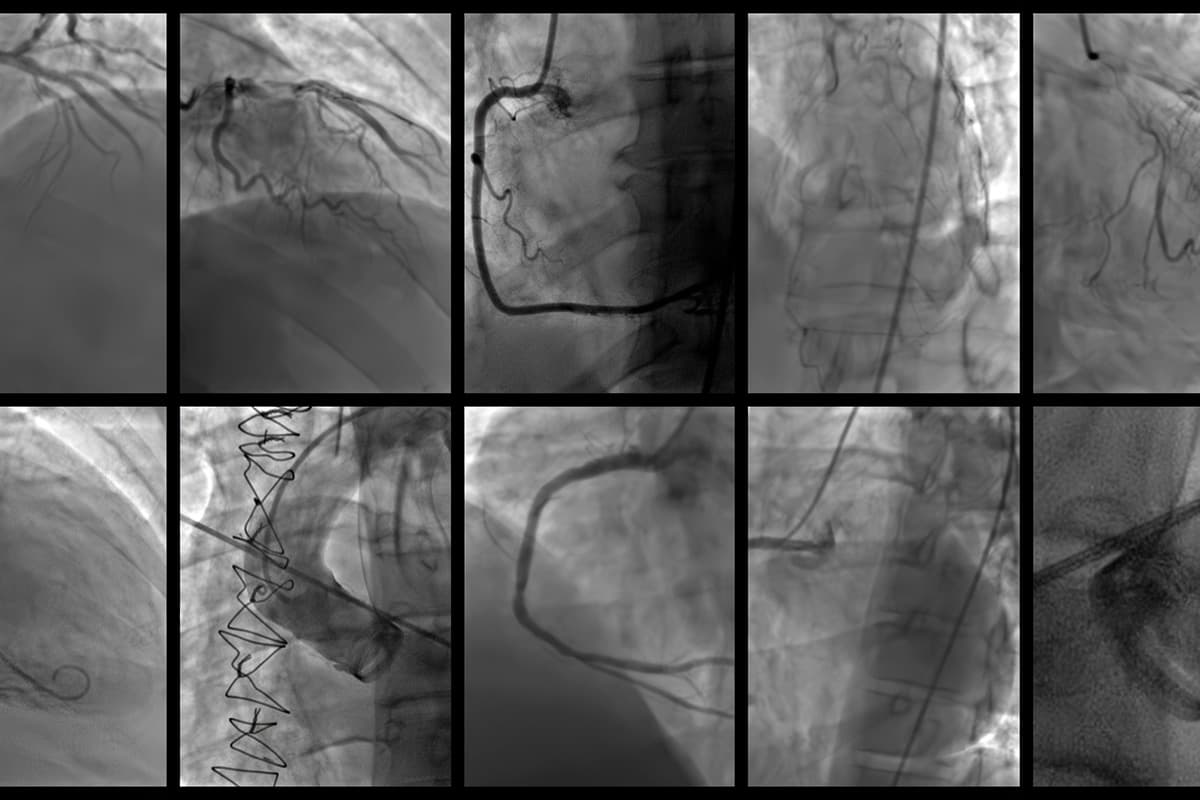

בדיקת סי טי לכלב או לחתול היא בדיקה המתבססת על טכנולוגיות רנטגן והיא מספקת תמונה של כלל הגוף. בבדיקה מיוצרת סדרת תמונות המספקות חתך רוחב של הגוף. תמונות אלו מעובדות באמצעות מחשב ליצירת תמונה תלת-ממדית מפורטת ביותר של האיברים השונים, העצמות, כלי הדם והרקמות הרכות.

בדיקת סי טי מעניקה מידע מבני מדויק ביותר, והיא מאפשרת אבחון של מגוון רחב של מחלות ופתולוגיות, ביניהן:

- גידולים ושינויים באיברי הבטן, בעמוד השדרה, בעצמות ובמוח

- פריצת דיסק בעמוד השדרה

- אבחון בעיות אורטופדיות מורכבות בעצמות ובמפרקים

- זיהוי גידולים בריאות, גרורות, דלקות ריאות מורכבות, זיהומים וגופים זרים בדרכי הנשימה

לכן, בדיקת סי טי גם נמצאת בשימוש בכלל תחומי הרפואה- פנימית, אורטופדית, כירורגית ונוירולוגית. את הבדיקה עושים וטרינרים רדיולוגים, והיא נעשית בהרדמה ודורשת לפעמים הזרקה של חומר ניגוד.

בבדיקת סי טי לכלבים וחתולים עושים שימוש במקרים שבהם נדרש פירוט נוסף וחד יותר להדמיית האיברים הפנימיים, להדמייה מיטבית של כלי הדם באמצעות חומר ניגודי כשיש חשד לגידולים בחלל בית החזה ובריאות ובכל מה שקשור לרפואה האורטופדית והנוירולוגית- מה שכולל הדמיית עצמות, עמוד השדרה והמוח, וזה לא מתאפשר בבדיקה סונוגרפית.